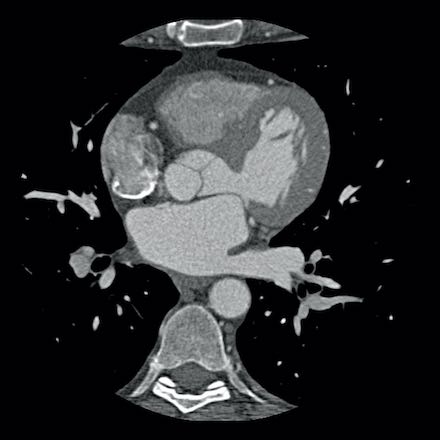

case 2 – CAD-RADS 5/P2/S

First, scroll through the CTA images.

How would you describe the findings on the coronary CTA?

The findings are:

- Stent in the mid

LAD with low-attenuation within the stent suggestive of minimal in-stent

restenosis (<25%). Non-calcified plaque distal to the stent

causing mild stenosis (25-49%). Notice bridging on a short segment in

the distal LAD. - Non-calcified

plaque in the LCX causing mild stenosis (25-49%). - Occlusion of the

proximal OM1 branch with distal filling. - Calcified and

non-calcified plaques in the proximal RCA causing mild (25-49%) stenosis. - Total plaque burden

is moderate based on SIS (four segments including proximal RCA, mid LAD, prox

LCX and OM1).

Due to the occlusion of OM1 branch and presence of the stent, this case

reads as CAD-RADS 5/P2/S, which means that this patient needs further

diagnostic workup.